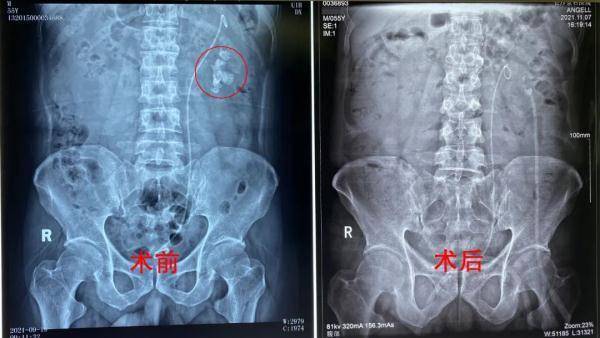

文章图片

▲张先生术前术后腹平片对比图

10月27日 , 张先生顺利办理入院后 , 接受了详细的术前检查 , 确诊患有左肾铸型结石32*13mm、左输尿管上段结石、左肾积水 , 左肾陷入危机 , 必须尽早处理 。

10月29日 , 张先生顺利接受了手术 。 卢卓雄介绍:“他的手术方案我们经过反复的讨论才定下来 , 就是为了减少手术次数、利用一个通道做到取石效率最大化 。 ”目前 , 张先生的左肾结石基本已清除 , 左肾中的结石和积水危机已解除 。